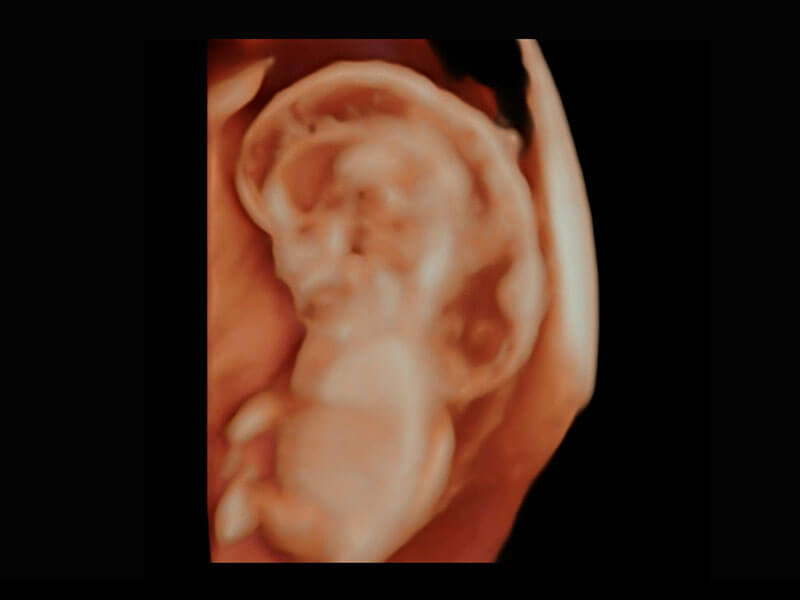

P60在胎兒早孕期超聲篩查中為您帶來(lái)優(yōu)異的圖像質(zhì)量。

早孕-胎心